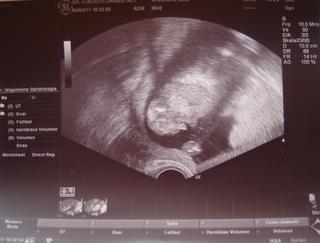

veru, je to úžasný pocit, keď ho môžem vidieť, dr. je zlatý, robí mi sono každý mesiac, aj keď aj tu sú tak ako na SK len 3 utz povinné a preplácané poisťovňou, ale nejako to nerieši. fotku mám, aj ju sem teda dám, ale je dosť o ničom, keby nám to dr. pekne neukázal, tak ani neviem, čo je čo 😉

takže bábo má vpravo hlavičku, takú zvesenú a cmúľa si ruku...no a tam dole to vytrčil 😀 😀 😀 a nad tým ešte trošku trčí šnúra. a také to guľaté vpravo dolu je nožička. tak hádam sa to s popisom dá 😀

@jajus áno Janka, bude to chlapček, už som si to aj do pasu dala, dr. povedal, že je to na 99,9 % a aj sme teda videli dôkaz 😀 ďakujem 😵

ahojte, tak aj vám sa musím pochváliť, včera sme mali krásne predstavenie a už vieme 😉 ivke vyšiel tip č. 2 😉 😀